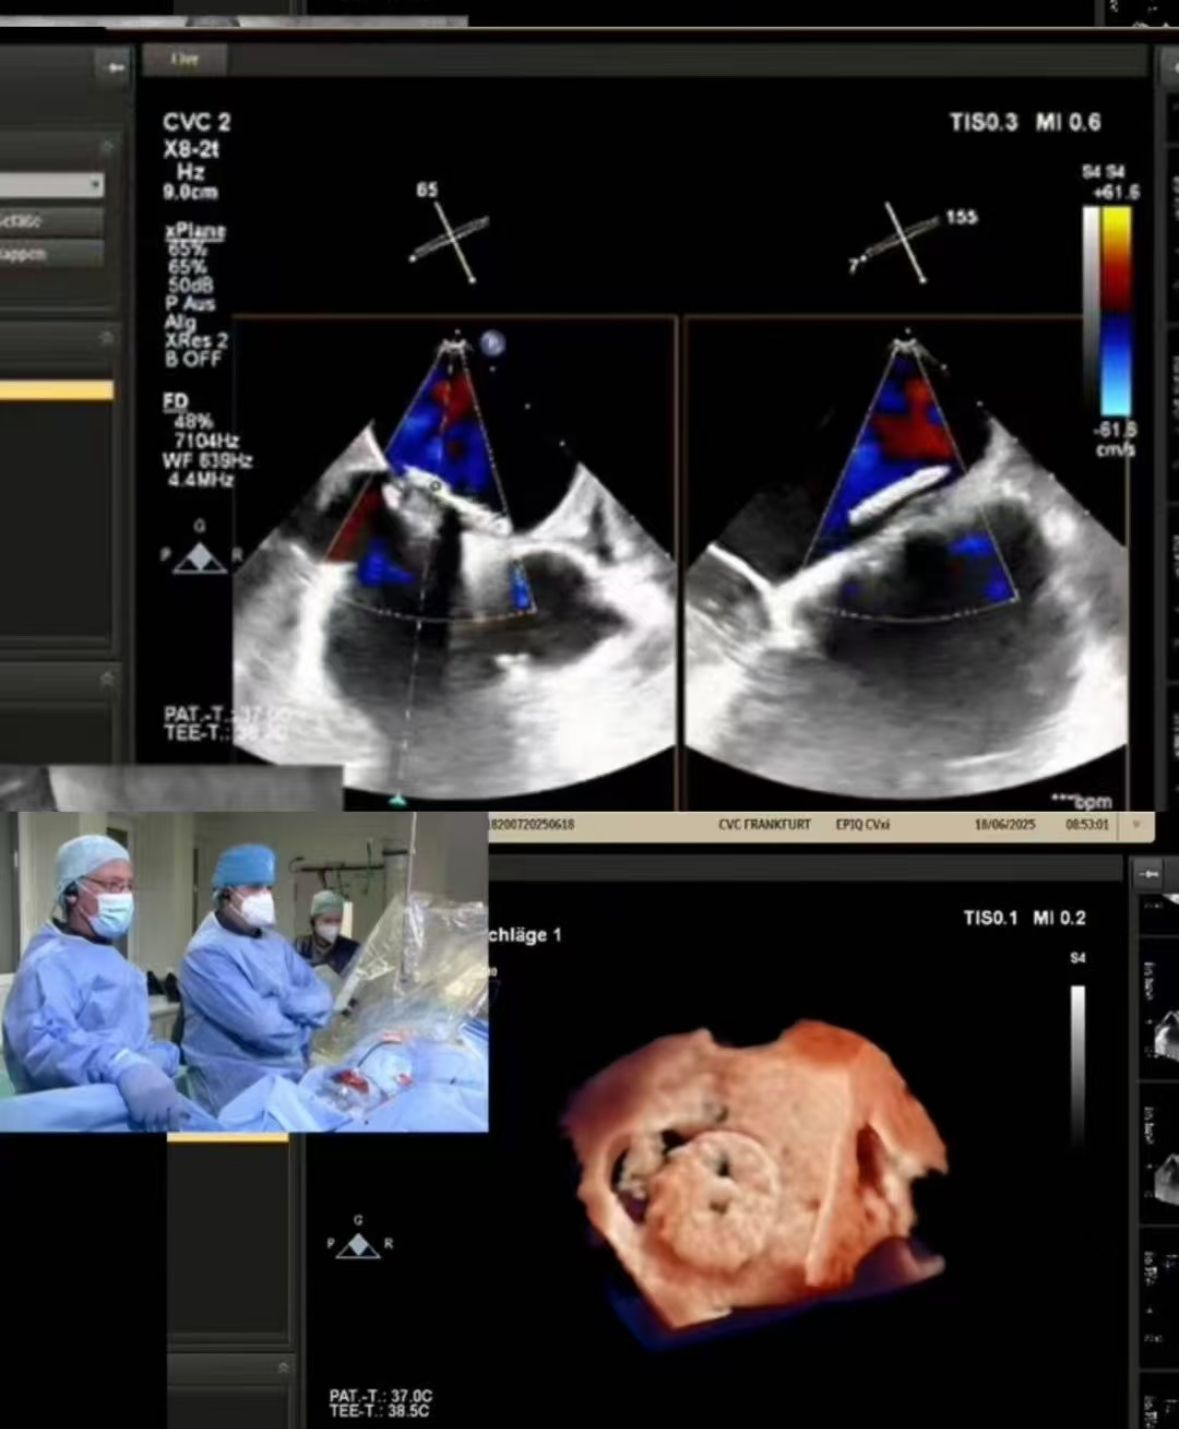

Thrilled to showcase our MemoSorb PFO Occluder – the world's first absorbable device (degrades to water & CO₂ within 1 year) – during a live broadcast from the Blue Room at CSI Frankfurt!

Nous avons diffusé une fermeture de PFO complexe réalisée à CVC Francfort sur une patiente âgée de 60 ans avec:

1. AVC emboliques récurrente (2014, 2021)

2. allergie sévère au nickel (contre-indication pour les dispositifs métalliques)

3. shunt résiduel après la fermeture antérieure

2. fermeture précise: l'imagerie en temps réel a guidé le déploiement parfait dans l'anatomie provocante (fenestration de tunnel de PFO).